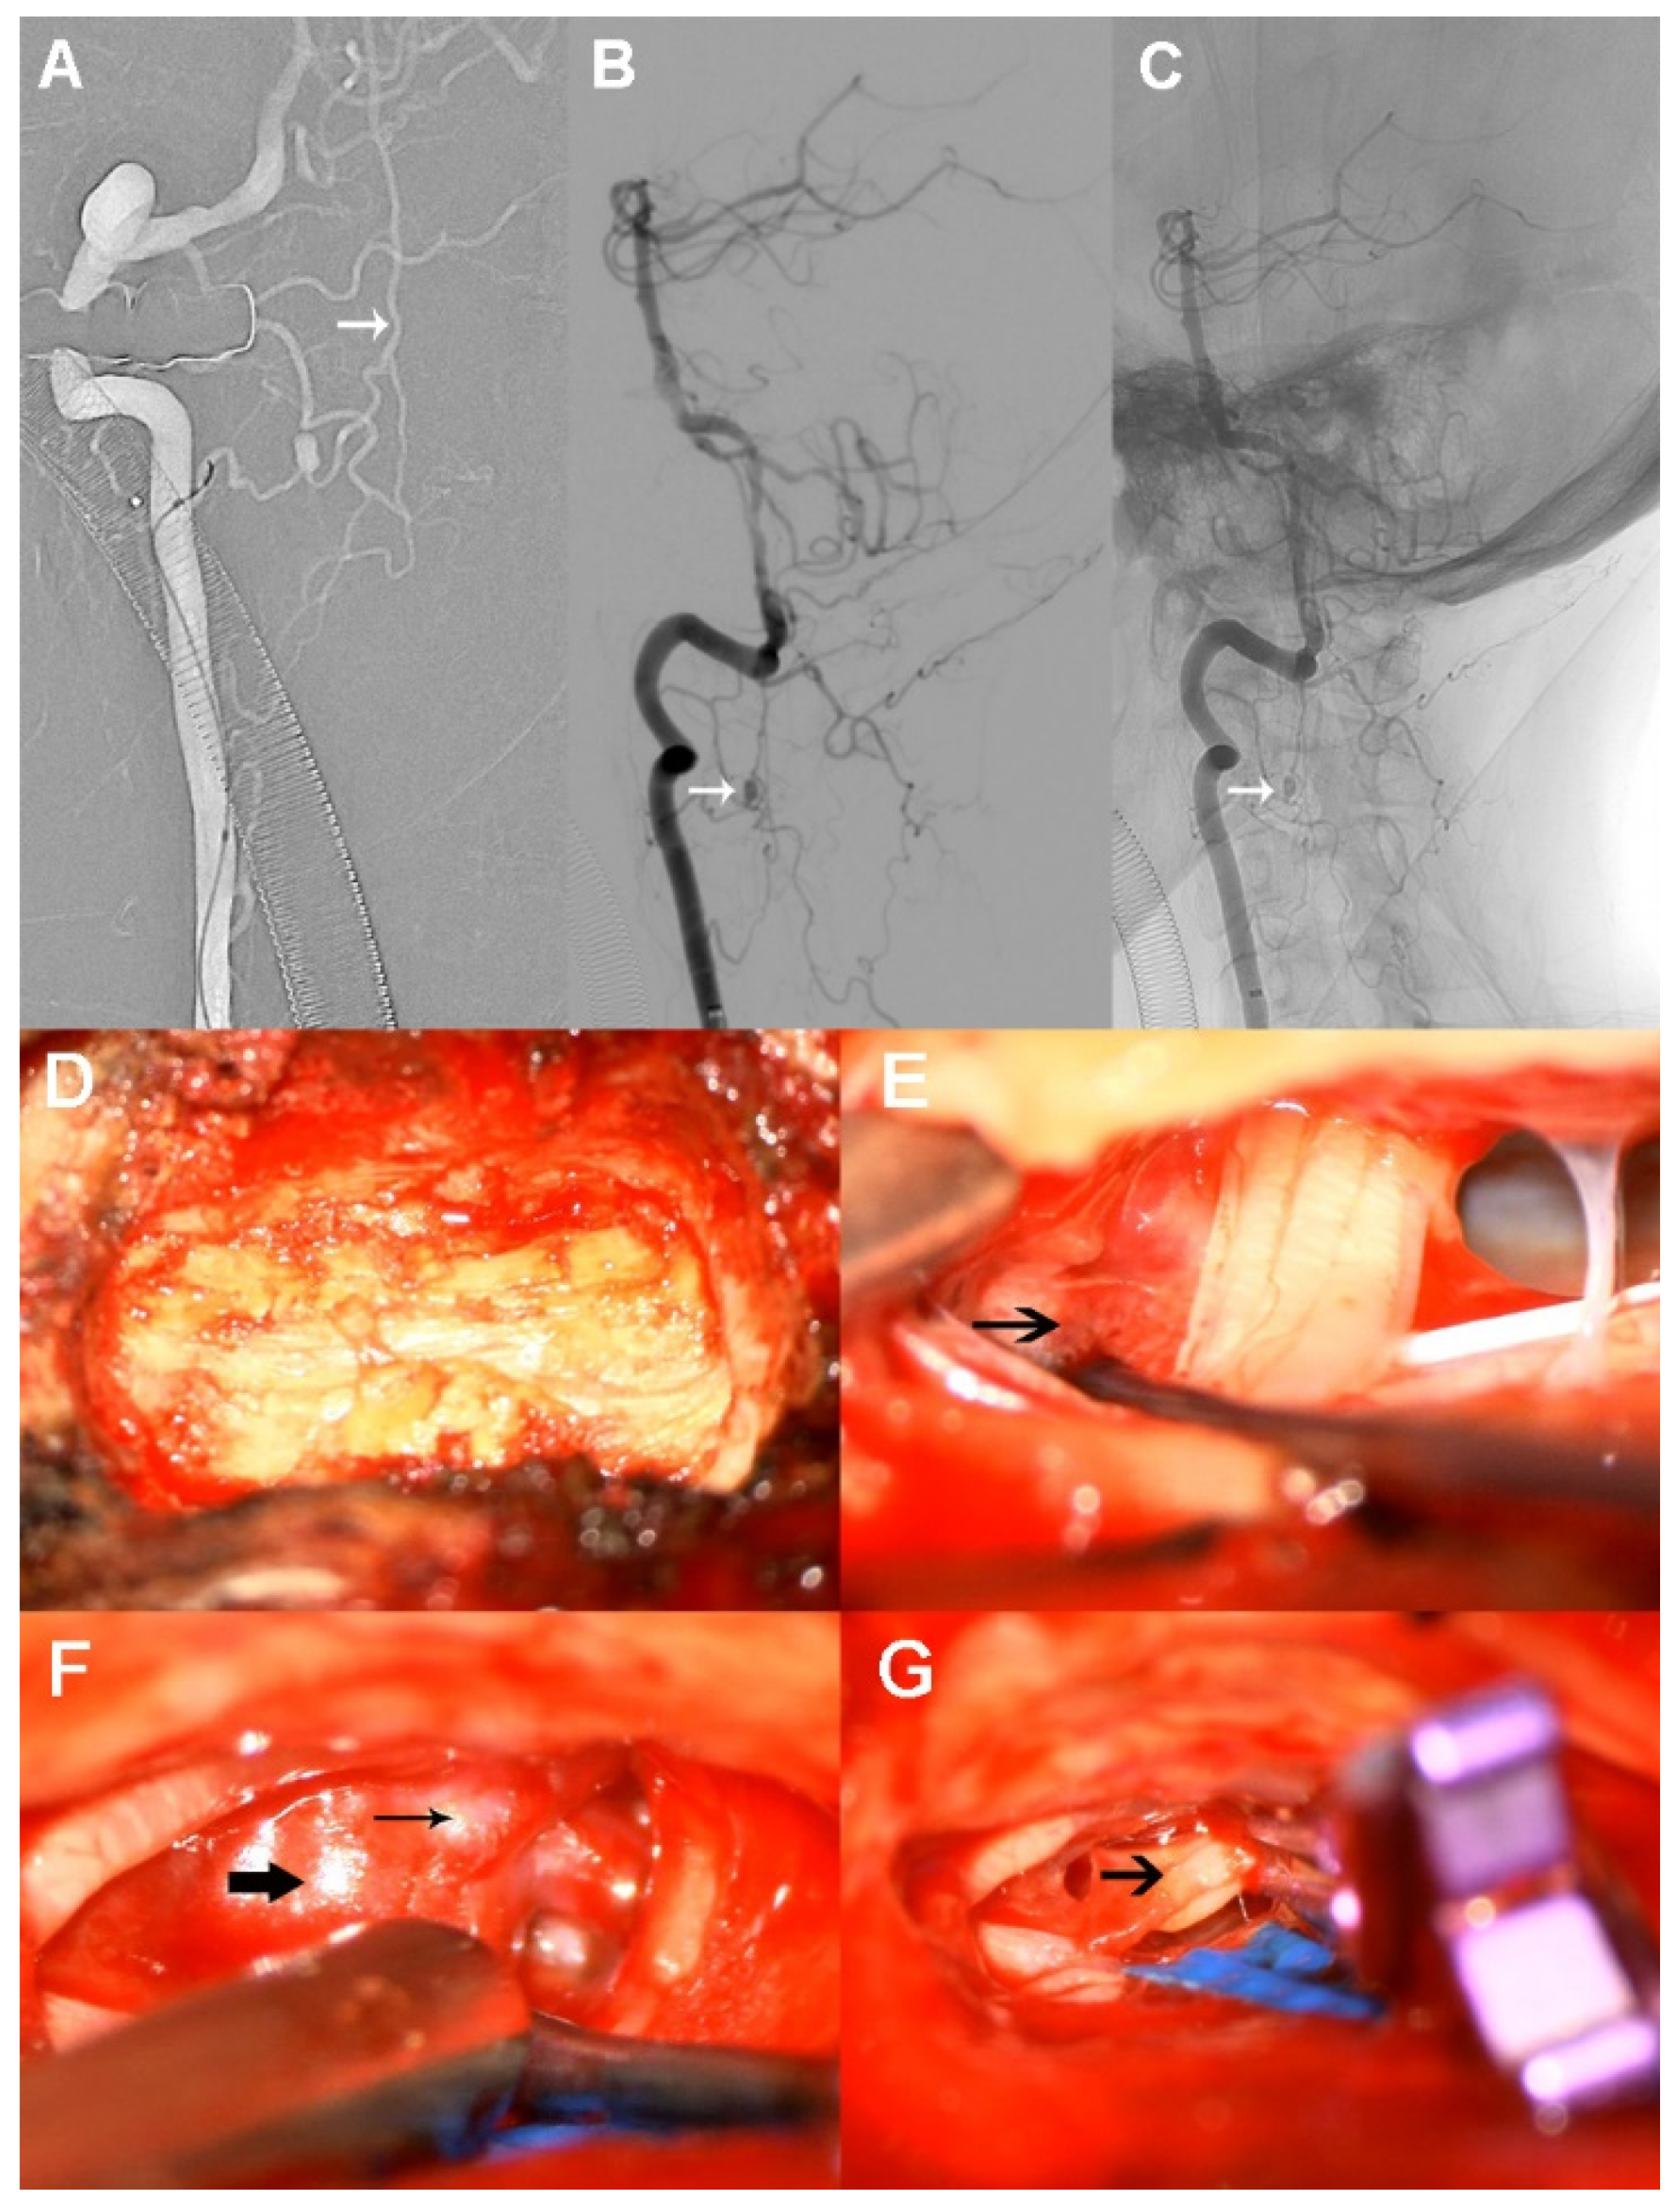

We then scheduled this operation in a hybrid OR. Initially, we attempted to achieve endovascular coiling of the ruptured aneurysm from the right ascending cervical radiculomedullary artery instead of the straight anterior spinal artery, as we were concerned about the possibility of arterial occlusion during the intervention. A 5 French guiding catheter was first placed in the V2 segment. However, we found obvious contrast agent retention, suggesting limited blood flow caused by severe vasospasm. Then, we pulled the guiding catheter down near to the opening of the right VA. The tip of the marathon microcatheter was successfully guided into the proximal parent artery. However, it was hard to advance proximal to aneurysm because of inadequate catheter support. A microcatheter was then replaced with an Echelon-10 to provide stronger support, but it was similarly difficult to reach its target (Figure 3A). After several unsuccessful attempts, we resolutely terminated the endovascular procedure and immediately switched to operative clipping.

Figure 3.

Therapy processes in the hybrid operating room. (A) The tip of the microcatheter is successfully guided into the proximal parent artery. (B,C) As the arrows show, the aneurysm is located at the lower border of C2 centrum. (D) Right-side laminectomy. (E) Arrow shows dense blood clots around the ruptured aneurysm. (F) Parent artery (thin arrow) and aneurysm (thick arrow) are shown. (G) The ruptured aneurysm is completely clipped, leaving the sac wall to collapse (arrow).

The patient was further placed in a side-prone position and a small incision to the back of neck was applied. The aneurysm was located at the lower border of C2 centrum (Figure 3B,C). Accordingly, a right-side laminectomy was carried out via removal of two-thirds of C2 and one-third of C3 (Figure 3D). Bloody cerebrospinal fluid flowed out quickly when the arachnoid membrane was incised under microscopic magnification. Dense intradural blood clots were found around the ruptured aneurysm during surgery and were removed. As expected, the solitary ruptured aneurysm was identified on the anterolateral side of the spinal cord. The preservation of the parent artery was quite difficult because of the small diameter, so it was clipped completely together with the aneurysm using a mini-clip (Figure 3E–G). Finally, dural closure was finished by using an artificial dura mater. Unfortunately, we did not perform an immediate angiographic review postoperatively because the arterial sheath was accidentally pulled out when deciding to change the surgical procedure.